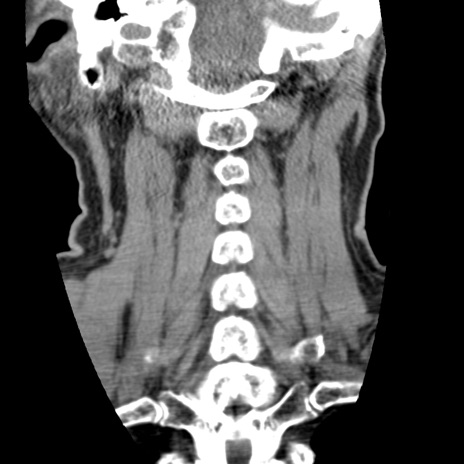

症例50 頚椎CT(冠状断像)

頚椎CT